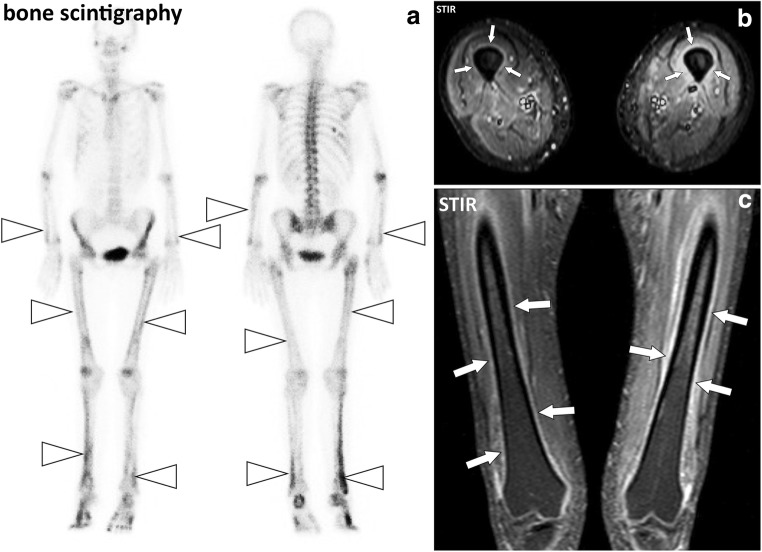

Fig. 17.

a Anterior and posterior whole-body bone scintigraphy, (b) axial and (c) coronal STIR images of the thighs of a 55-year-old female with pulmonary neoplasm and hypertrophic osteoarthropathy. Bone scintigraphy demonstrates symmetric linear increased uptake of tracer along the diaphysis and metaphysis of the long bones (arrowheads). MRI confirms periostitis with thickening and fluid signal intensity of the periosteum of the left femur and to a lesser degree of the right femur (arrows)